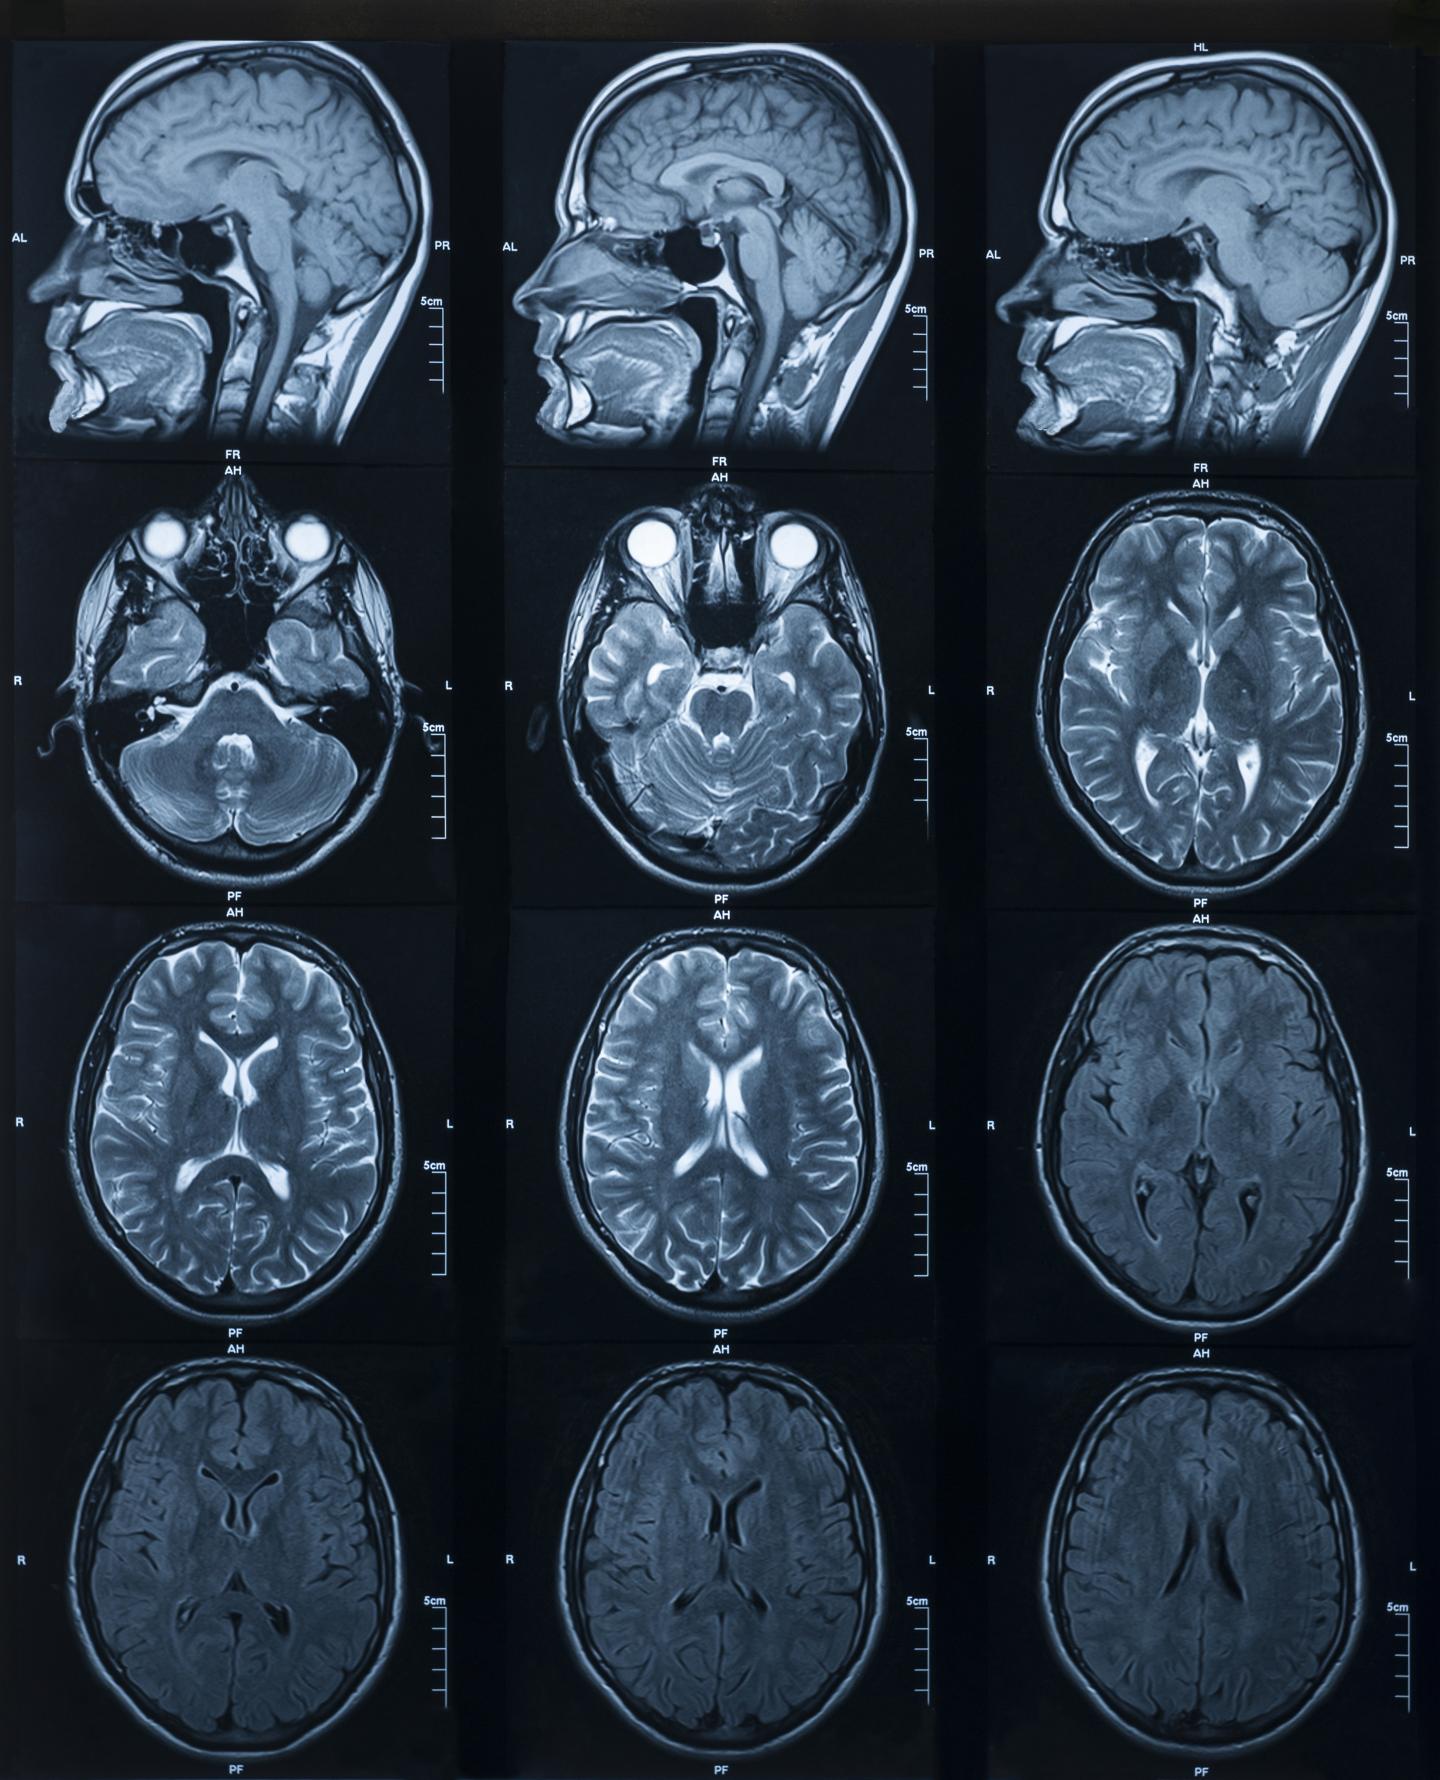

Ultra-high field MRI detects differences in brain's 'hippocampus'

image: Brain MRI images

CLEVELAND--Using ultra-high field magnetic resonance imaging (MRI) to map the brains of people with Down syndrome (DS), researchers from Case Western Reserve University, Cleveland Clinic, University Hospitals and other institutions detected subtle differences in the structure and function of the hippocampus--a region of the brain tied to memory and learning.

Such detailed mapping, made possible by the high-powered MRI, is significant because it allowed the research team to better understand how each subregion of the hippocampus in people with DS is functionally connected to other parts of the brain.

MRI scanners at ultra-high magnetic field strengths are increasingly available for human research, allowing neuroscientists to map the brain at higher resolution without losing image clarity.

Taking advantage of the increased resolution afforded by high-powered MRI, the researchers performed the first in-vivo comparison of volumes of different anatomical segments of the hippocampus between people with DS and "control" individuals of the same age and sex without DS.

"The gains in sensitivity and image resolution achievable with ultra-high field MRI provide levels of detail and accuracy that have not previously been attainable in studies of live, non-sedated individuals with Down syndrome," said Katherine Koenig, an assistant professor of radiology at the Cleveland Clinic Lerner College of Medicine of Case Western Reserve University and the study's first author.